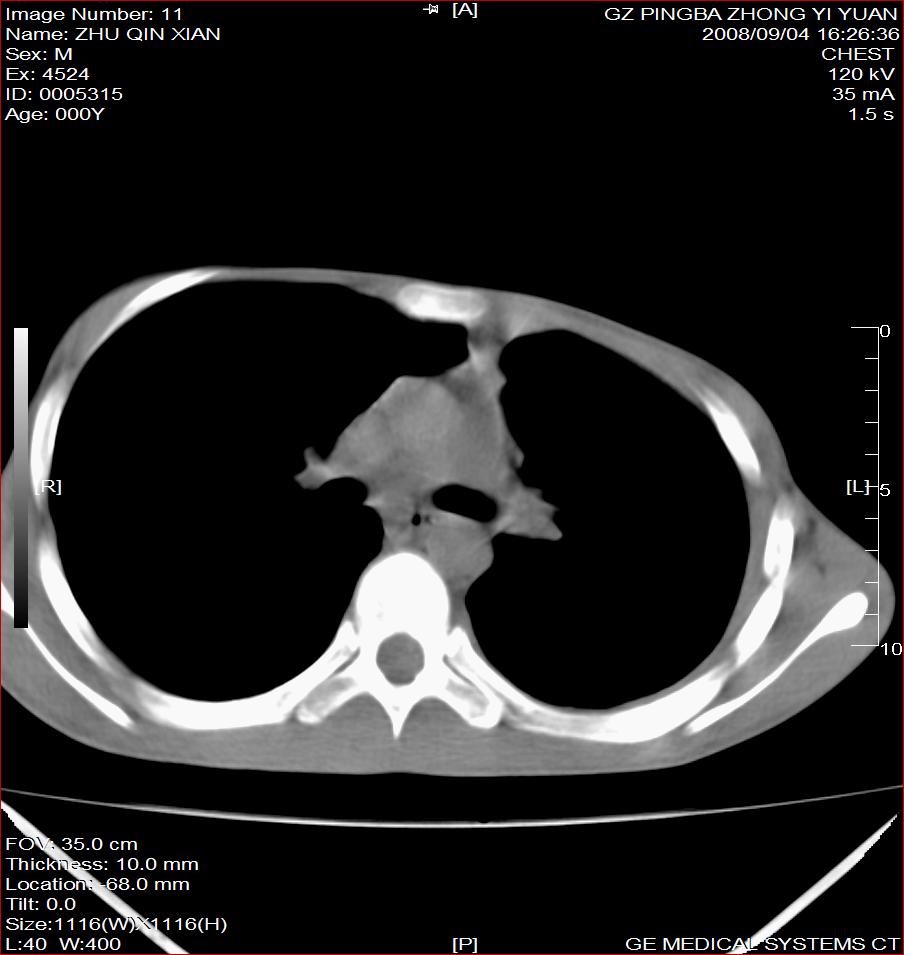

以下是引用随光逐影在2008-9-4 20:05:00的发言:[br]1)考虑两肺结核。2)左侧胸膜炎(胸膜肥厚、粘连,胸腔积液)。3)左侧局限性气胸。

以下是引用子十在2008-9-4 19:34:00的发言:[br]左上肺结核并空洞及双肺播散。节段性肺不张、胸腔积液、胸膜肥厚粘连。[br]